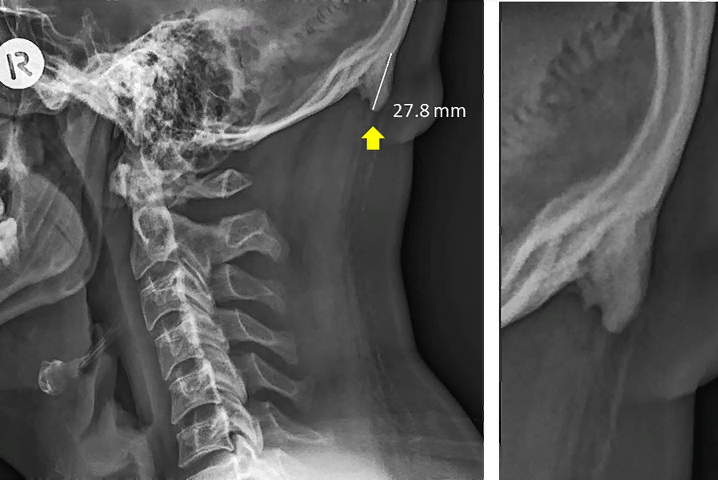

Известно, что необычные костные наросты, или костные шпоры, встречаются у людей пожилого возраста, но исследование, проведенное Дэвидом Шахаром и Марком Дж.л. Сэйерсом, выдвинуло новые и шокирующие детали. После сбора и анализа данных, полученных от 1200 человек обоего пола в возрасте 18-86 лет, было обнаружено, что по какой-то причине экзостоз, он же костные шпоры, растет у старших подростков и молодых взрослых, и число людей, с которыми это происходит, растет.

Довольно интересно, что эти костяные шпоры растут на задней части их черепов, и они похожи на рога. На самом деле, различные СМИ сообщали, что молодые люди выращивают “рога” на задней части своих черепов из-за их использования мобильных телефонов и других технологий в течение длительного времени, что является ложью. Даже если они выглядят как рога, они на самом деле не являются рогами, и это не мобильные телефоны, которые должны быть обвинены непосредственно.

Эта рогообразная костяная шпора была обнаружена более чем у 40% людей в возрасте 18-29 лет, и это довольно шокирует. Другой возможной причиной для той же проблемы может быть плохая осанка. Уже известно, что плохая осанка тела влияет на форму нашей скелетной структуры. Может быть, у некоторых молодых людей шея и позвоночник стали настолько воспаленными, что в теле растут новые кости, чтобы их поддерживать.